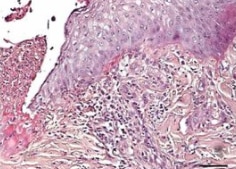

View Larger

Niemann-Pick Type C2/NPC2 in Human Kidney. Niemann-Pick Type C2/NPC2 was detected in immersion fixed paraffin-embedded sections of human kidney using Rabbit Anti-Human Niemann-Pick Type C2/NPC2 Antigen Affinity-purified Polyclonal Antibody (Catalog # AF8644) at 1:50 dilution overnight at 4 °C. Tissue was stained using the Anti-Rabbit HRP-DAB Cell & Tissue Staining Kit (brown; Catalog # CTS005) and counterstained with hematoxylin (blue). Specific staining was localized to cytoplasm in tubular epithelial cells. View our protocol for Chromogenic IHC Staining of Paraffin-embedded Tissue Sections.